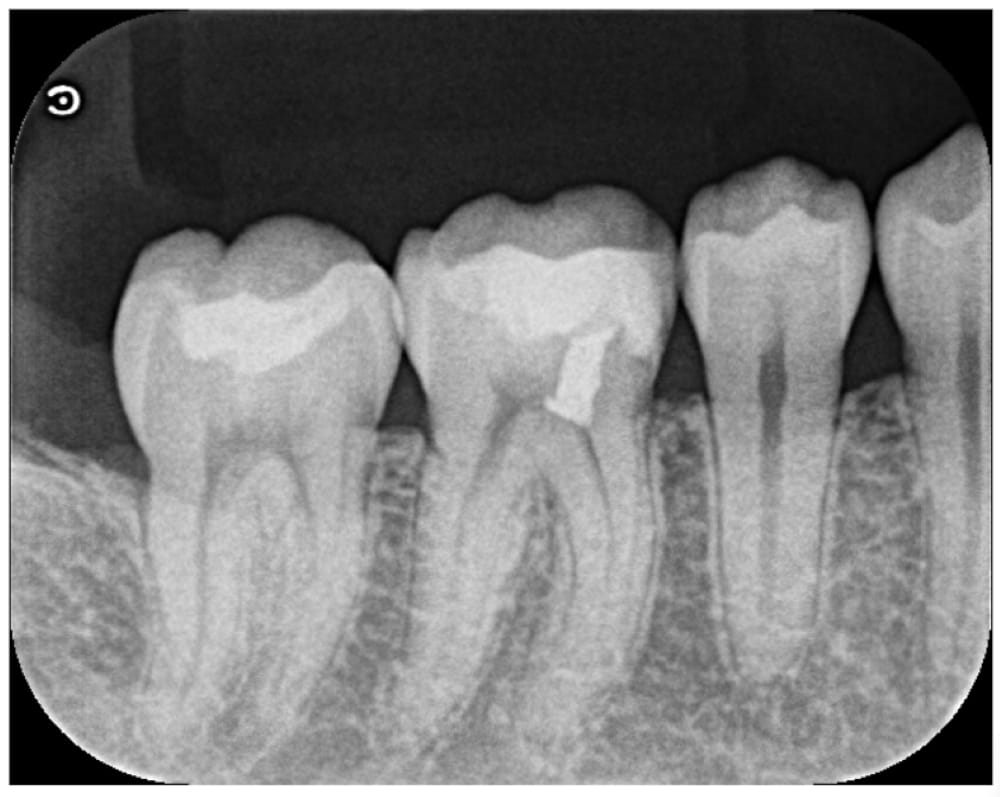

治療後6ヶ月

治療後の1〜2ヶ月はしみる症状があったものの徐々に軽減し、術後6ヶ月時点では自覚症状は消失していました。

歯髄の検査を行ったところ、正常な反応を示したため、セラミックインレーにて最終修復を行いました。